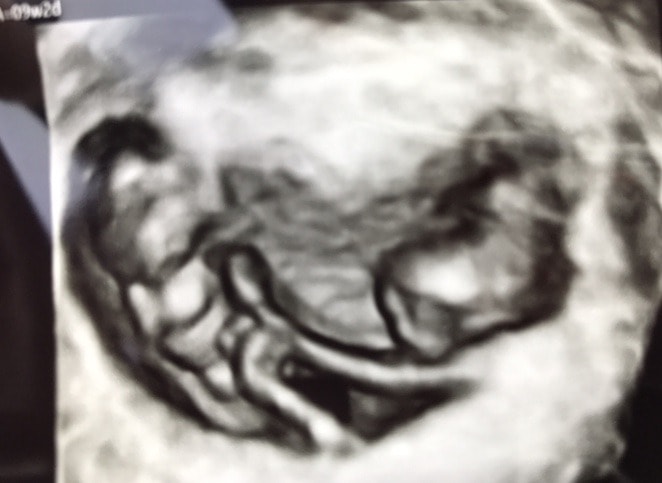

Ultrasound Photos of 9 Weeks Pregnant With Twins